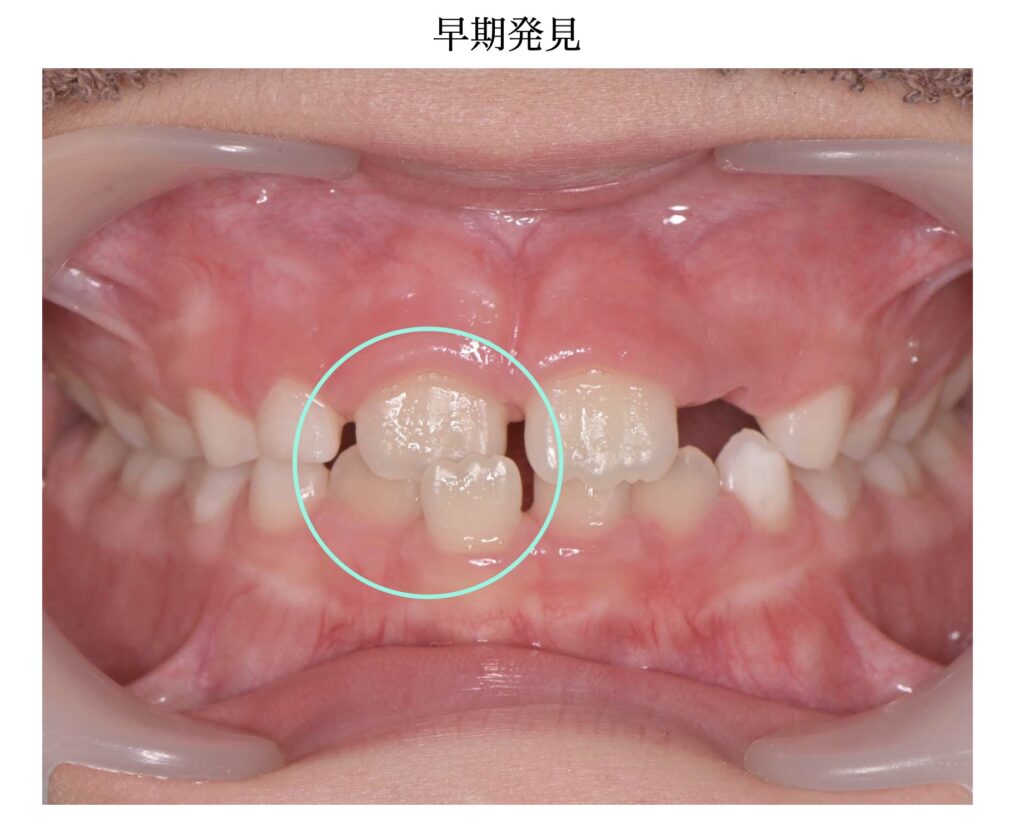

▼ 治療前|早期発見時

- 前歯の一部がクロスバイト(反対咬合)